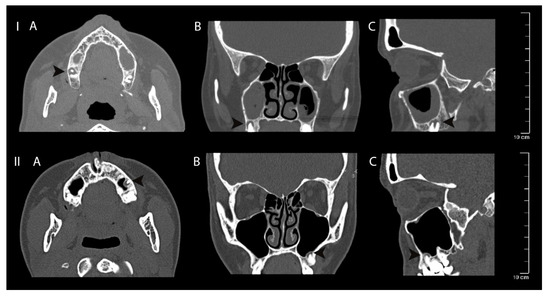

The detailed univariate multiple regression analysis of all independent variables on dependent maxillary sinus volume (mm3) changes can be seen in Table 4. An example of volumetric/2D analysis of maxillary sinus mucosa and periapical bone destruction is shown in Figure 4. Clinical case examples can be seen in Figure 5.

Figure 4.

Clinical case volumetric and two-dimensional analysis example. (A) segmented 3D view of maxillary sinus mucosa (red) and periapical bone lesion (blue); (B) cross-section of maxillary sinus mucosa, maximum thickening area; (C) 3D location of periapical bone destruction according to maxillary sinus mucosa with evaluation of highest diameter of periapical bone destruction and shortest distance between these structures; (D) automatic algorithm analysis of maxillary sinus mucosa thickening in mm (results are shown in coloured histogram: green—the lowest, red—the highest mucosal thickening).

Figure 5.

Clinical case I—mucosal thickening—advanced, periapical bone destruction size S3; Clinical case II—mucosal thickening up to 2 mm, periapical bone destruction size S3. Computed tomography axial (A), coronal (B) and sagittal (C) views of apical periodontitis around the roots of the teeth and maxillary sinus mucosa thickening. The lesions are indicated with black arrows.